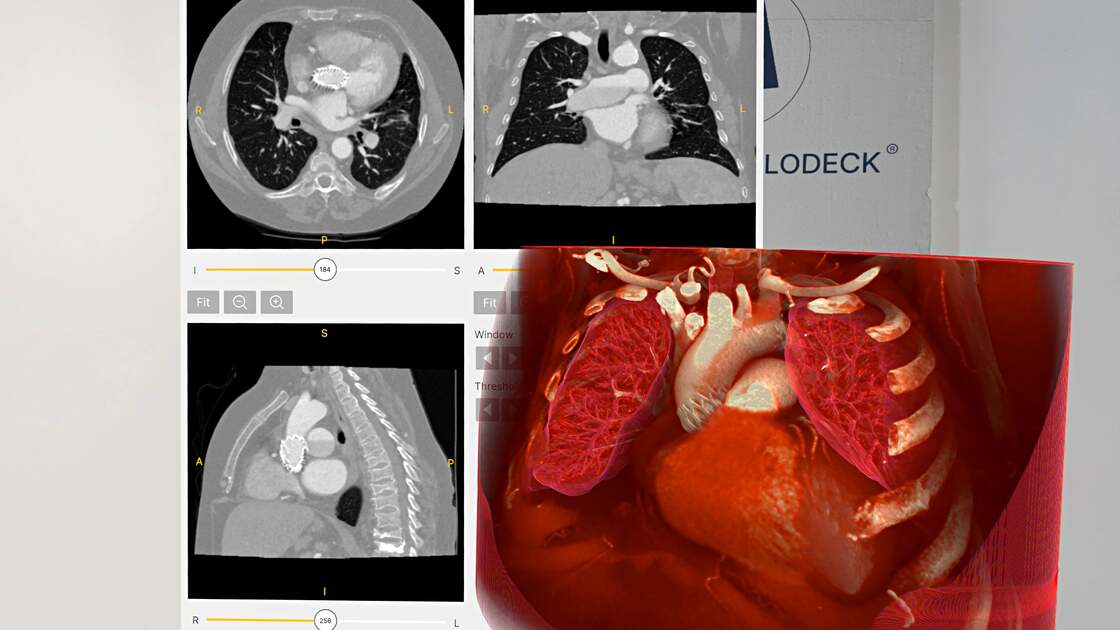

Multi-planar reconstruction (MPR) viewing, more powerful MRI tools, new Anatomy Master models, enhanced presets, and DICOM PUSH expand the platform’s capabilities.

We have just released Medicalholodeck version 1.5.0, now available on all platforms. This update introduces powerful new segmentation tools, a refreshed user interface, and key stability improvements – making your VR and AR experience more precise, flexible, and reliable.

Animated medical imaging plays an important role in thoracic and cardiac surgery. Medicalholodeck now allows the import of animated, 4D medical imaging from CT, MRI, and echocardiography. Used in virtual reality, 4D data adds significant value to surgical planning, training, and education.